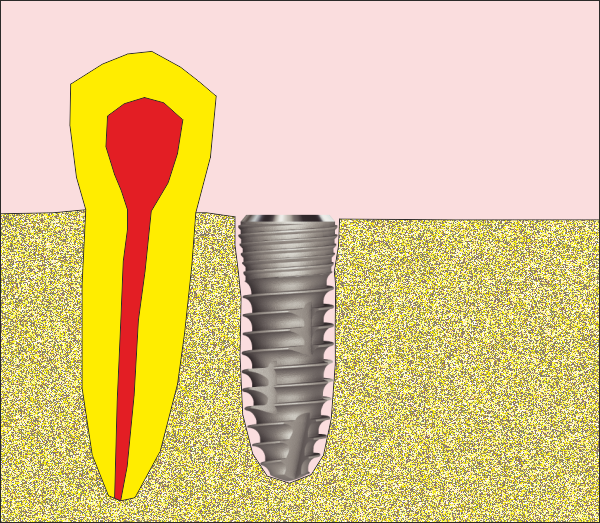

На горната снимка се вижда къс имплант с широк диаметър, подходящ за имедиатно имплантиране. В областта на имплантатната шийка има разширение, което изпълва алвеолата и в много случаи не остава костен дефект - няма необходимост от костна пластика. Зъбният имплант на горната снимка е от серията Superline на производителя Dentium от Южна Корея. Тази имплантатна серия много прилича на серията IS1 на производителя Neobiotech, описана по-долу.

Схема на имедиатно поставен зъбен имплант от серията IS1 на производителя Neobiotech.

Вижда се как формата на импланта наподобява формата на зъбния корен - съответно

на зъбната алвеола след екстракцията на зъба при еднокоренови зъби. При

многокоренови зъби разширението на имплантатната шийка също е от полза по

отношение на имедиатното поставяне, но е необходимо да се използва доста

по-широк зъбен имплант - поне два пъти по-широк от диаметъра на корена, тъй като

долните молари са с по два корена, а при горните има също два във всяка една

равнина. Обикновено при горните молари палатиналният корен е доста по-голям

диаметър от останалите и поради това доста зъболекари препоръчват именно на

неговото място да се поставя зъбен имплант при имедиатно имплантиране. Нашият

екип не препоръчва подобен подход - в действителност диаметърът на корена е

доста голям, но при поставяне на импланта на неговото място протетичният

резултат впоследствие не е добър. Необходимо е да се изработи корона с много

голям екватор с всички негативни последици от това - трудно почистване и

опасност от постоянно разциментиране.